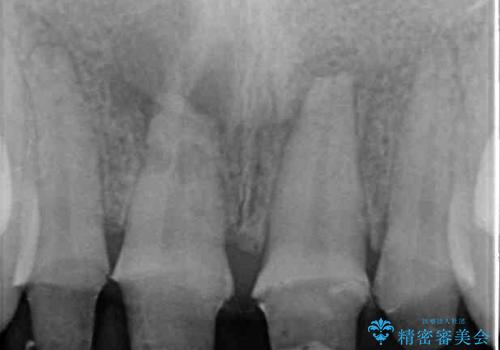

右側前歯は歯根が短くなり、パンチング状に歯根に透過像が認められたため、予後不良と判断し抜歯することとしました。

当初のレントゲン写真では根尖部に骨透過像が認められた両サイドの2歯は、歯髄の正常な反応が認められたためそのまま保存し、左側前歯は歯髄が失活していたため根管治療を行うこととしました。

事故直後のレントゲン写真では全ての歯の根尖部に骨透過像が認められましたが、治療後には全ての透過像がなくなっていました。